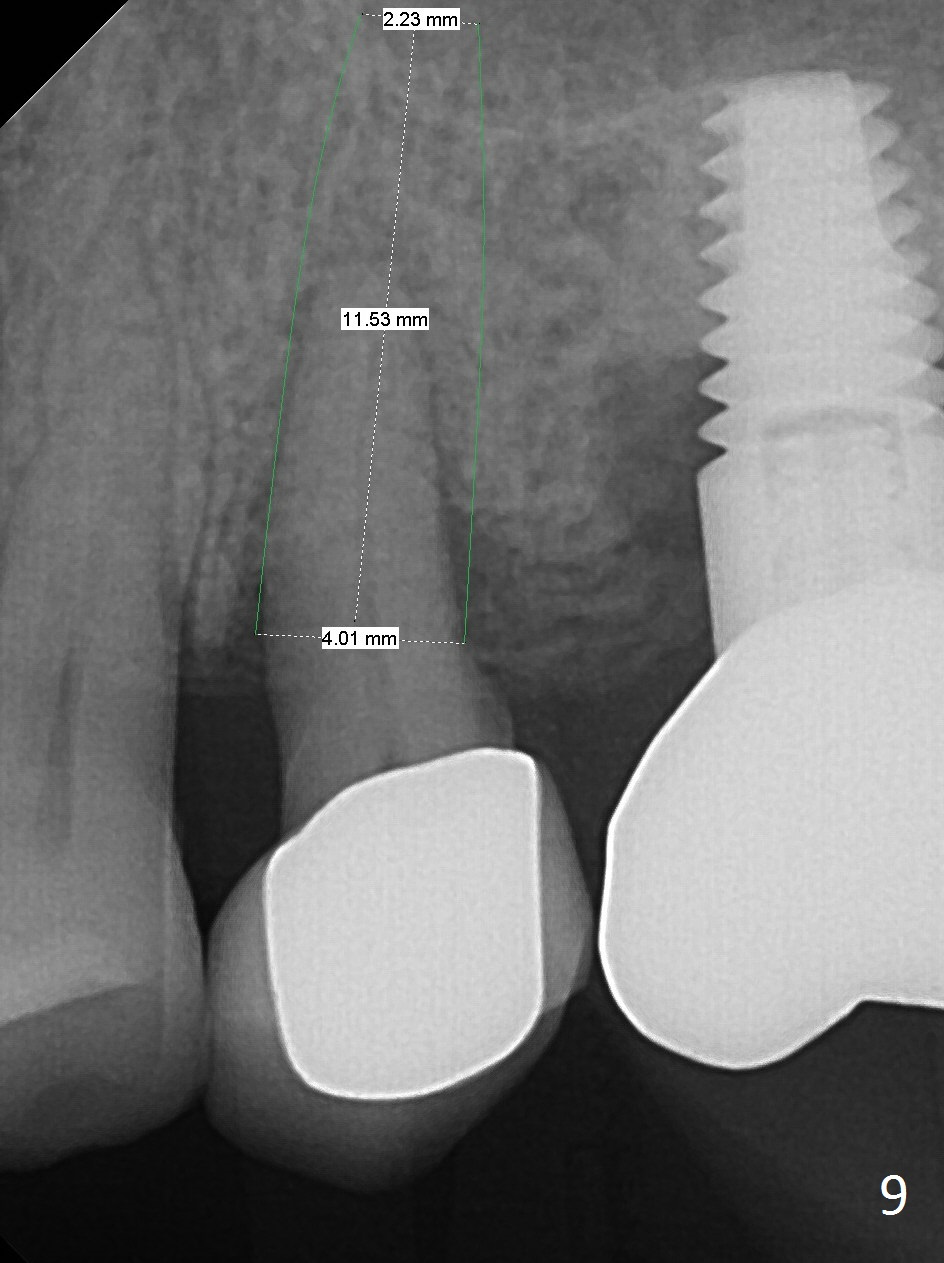

To compensate for bruxism, the implant at #13 should be as large and long as possible.  After extraction (Metronidazole), take PVS impression of the socket.  Start osteotomy in the distal wall of the socket (Fig.7 red).  The initial depth is 11 mm (gingival level).  Increase the depth once the trajectory is confirmed (Fig.9).  After implant placement (Fig.8 green), place bone graft (red circles) in the mesial portion of the socket as well as in the coronal portion of the implant at #14 (incision).  Use a healing abutment (pink), collagen plug (yellow) and suture to close the socket opening.